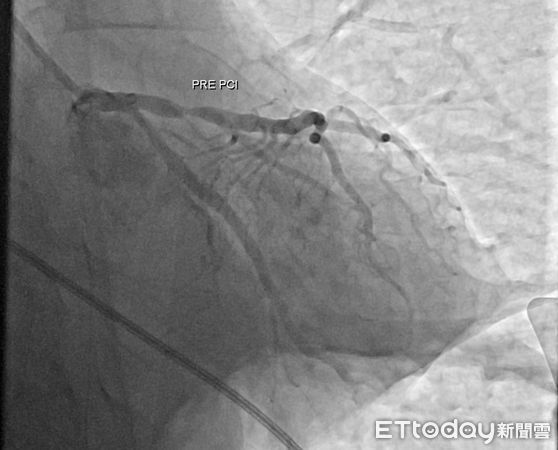

▲病患接受緊急心導管發現左前降支有一危險狹窄。(圖/嘉義醫院提供)

急診醫護團隊第一時間施行高品質心肺復甦術(CPR)、電擊除顫及氣管插管等緊急處置,成功讓患者恢復自主心跳,並迅速轉入心導管室,由心臟內科羅勖中醫師緊急接手治療。經心導管檢查發現,患者左前降支(LAD)幾乎完全阻塞,為典型導致猝死的致命型心肌梗塞。羅醫師果斷進行冠狀動脈介入治療,於極短時間內開通阻塞血管並植入支架,有效恢復心肌灌流,爭取到救命的黃金時間。